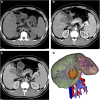

As a rare disease, intrahepatic sarcomatoid cholangiocarcinoma (s-CCC) represents less than 1% of malignancies of the hepatobiliary system and its main clinical symptoms include abdominal pain and fever. Results of pathological examinations, despite being the "gold standard", can easily be confused with hepatocellular carcinoma (HCC). This report is about a 32-year-old male patient who was hospitalized due to occupancy of segment V of the liver for three days and had a history of chronic hepatitis B (CHB) over a 20-year span. Magnetic resonance imaging (MRI) showed a 43 mm × 52 mm-sized liver mass in the V segment, with patchy peripheral enhancement during the arterial phase and rapid wash-out during the portal and late phases. A laparoscopic hepatectomy of segment V, along with cholecystectomy, was performed. Histopathological and immunohistochemical examinations indicated a malignant neoplasm that was positive for vimentin and cytokeratin, with these features providing a positive diagnosis for intrahepatic sarcomatoid cholangiocarcinoma. After surgery, an adjuvant therapy of albumin-paclitaxel combined with gemcitabine regimen was given. No recurrence was found six months after the surgery, with follow-up still ongoing. This report aims to improve the awareness, diagnosis, and treatment of s-CCC.